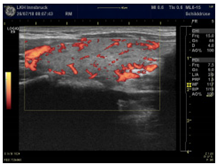

| Moderate increase with a wire-like pattern—suggests CoQ10 deficiency | |

| Very intense hyper-perfusion—suggests a severe combined deficiency condition | |

| Power Doppler Images | ![]() | ![]() | ![]() |

| Condition | Magnesium def. pattern | CoQ10 def. pattern | Chronic fibrosis |